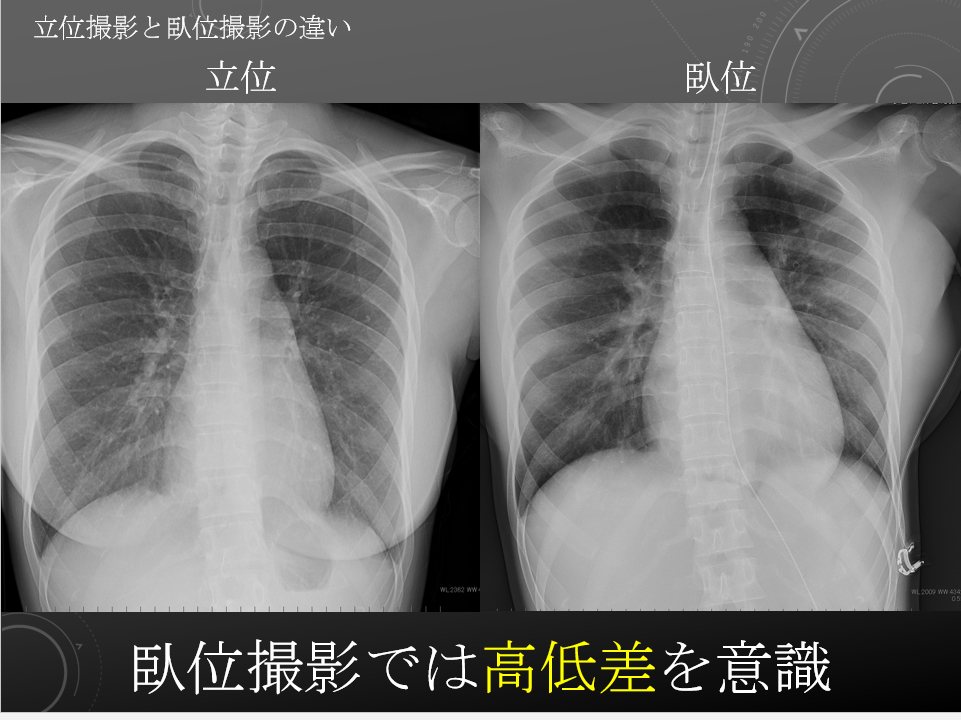

臥位と立位

臥位と立位